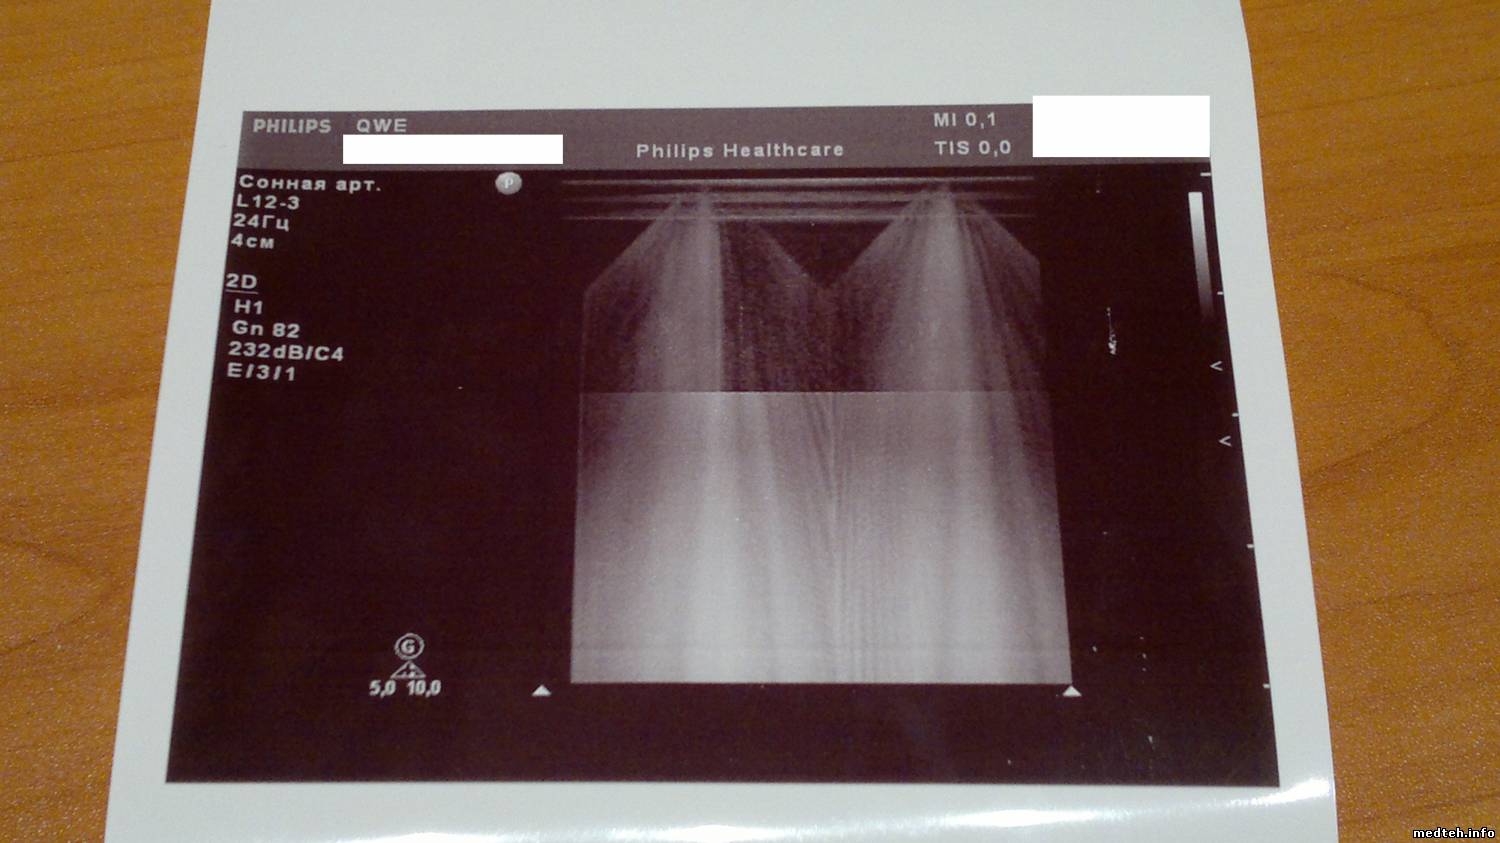

При тестировании аппарата выявились косяки с вагинальником и линекой-наложение серого фона/наводка(не знаю как обозвать), см. фото ниже.

Собственно нужно быть уверенным что дело в датчиках,а не в аппарате.Смущает симметричность наложиний серого на линейке. На вагинальнике нормально кажет только 1/5 часть всего сектора. Да, и к каждому датчику в упаковке шла распечатка с фантома-всё красиво и чётко. Вся упаковка цела, внешних/механических дефектов нет.

1367691.jpg (121.1 Kb) · 9129443.jpg (125.6 Kb) · 5411872.jpg (104.1 Kb)